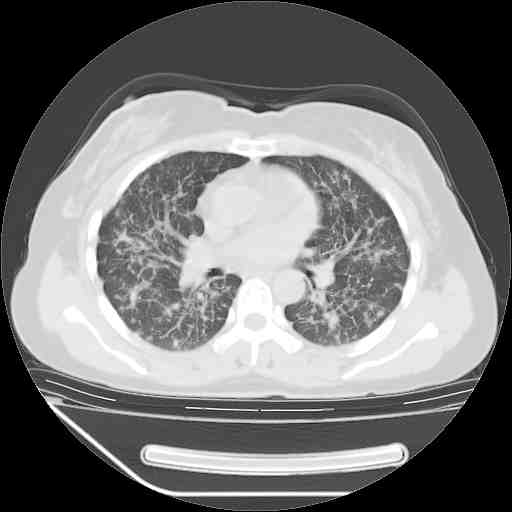

支持肺癌并肺内淋巴管转移,

支持肺癌并肺内淋巴管炎,  原发灶小了,但转移较前片明显了.

标准的细支气管肺泡癌呀!治疗后病情有所控制,也没治愈的迹象!

标准的癌性淋巴管炎!!距大去之日不远已.